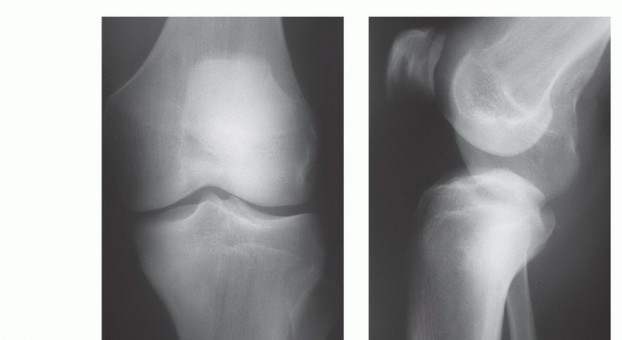

صورة شعاعية تظهر ساركوما عظمية في قصبة الساق القريبة لمريضة تبلغ من العمر 17 عاماً.

صورة شعاعية توضح ورماً عظمياً في قصبة الساق القريبة.

صورة شعاعية جانبية توضح ساركوما عظمية في قصبة الساق القريبة.

صورة شعاعية تظهر تدميراً قشرياً وامتداداً للأنسجة الرخوة للورم.